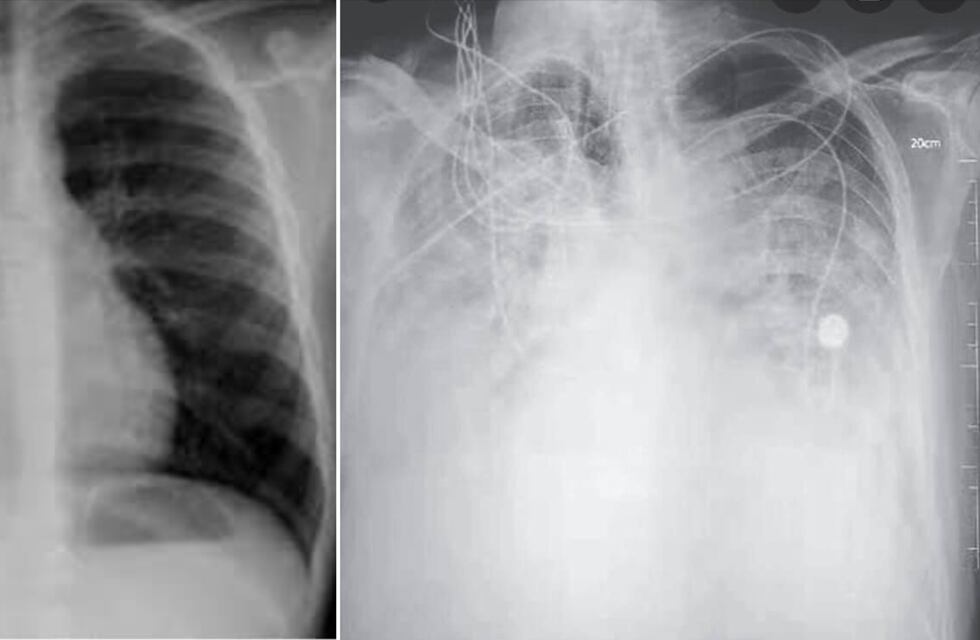

Luego de las imágenes del fin de semana en la que se vio a cientos de jóvenes en fiestas sin distanciamiento, la doctora del Hospital Pintos, Romina Perli, publicó en Facebook dos imágenes más que impactantes: una radiografía de tórax normal y otra de un paciente COVID.

“No quiero herir susceptibilidades y menos pelear con nadie. A la izquierda una radiografía de torax normal; a la derecha una radiografía de un paciente covid. Para que lo entiendan, no te queda pulmón, no podés respirar”, aseguró la emergentóloga en su cuenta personal de Facebook.

“Que seas joven y sin factores de riesgo, ni patologías previas; no te hace inmune o exento de que tengas la evolución tórpida de terminar en asistencia respiratoria mecánica. Imagínate tus familiares mayores. Nosotros seguimos muy cansados; pero no por ello bajamos la guardia. Solo te pido usa el barbijo, distanciamiento y conciencia social. No queremos seguir lamentando más pérdidas”, concluyó Perli.